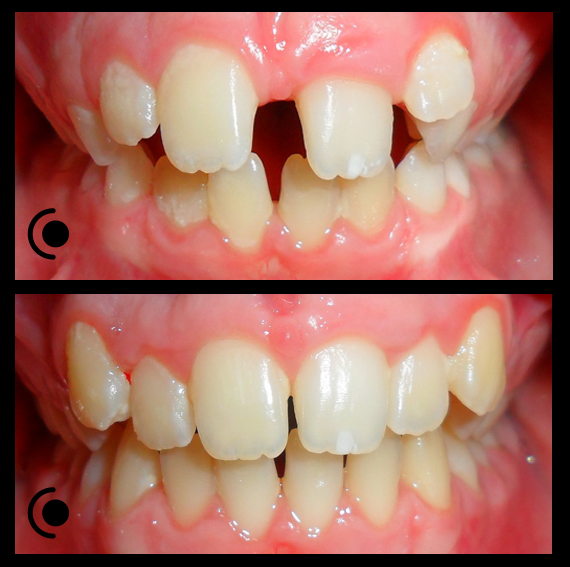

O našoj kvaliteti najbolje govore naši rezultati!